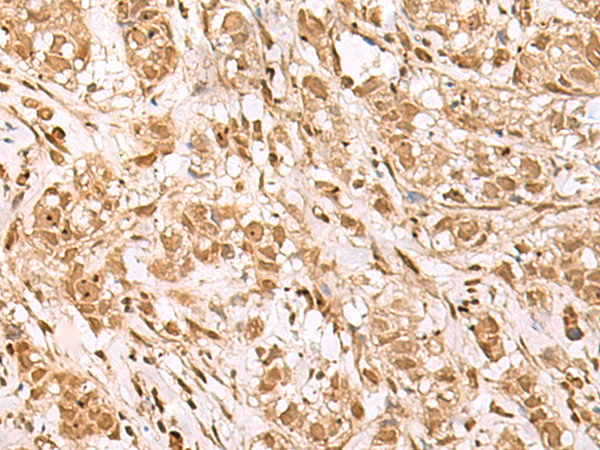

IHC positive control: |

Human esophagus cancer and Human breast cancer |